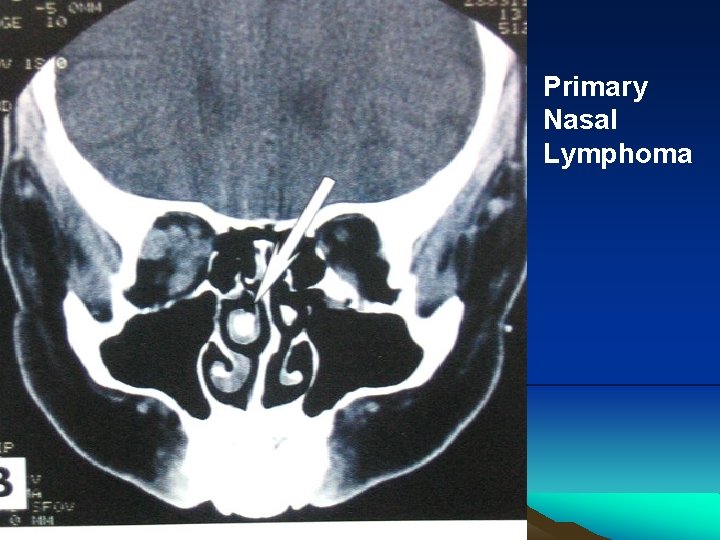

Sinus Lymphomas

Primary Nasal Lymphoma